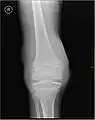

L'hémarthrose est un épanchement de sang dans une cavité articulaire consécutif d'une lésion ligamentaire, d'une fracture osseuse ou encore d'une atteinte du cartilage osseux[1]. Cette physiopathologie est caractéristique des personnes atteintes d'hémophilie sévère et dans une moindre mesure chez les formes modérées, car chez les hémophiles, l’absence ou l’altération d’un des facteurs de la coagulation (VIII ou IX selon le type d’hémophilie) perturbe le processus de la coagulation, au point qu’un traumatisme minime peut provoquer un saignement prolongé[2]

Près d'un quart des lésions sévères des ligaments et des genoux capsulaires entraînant une hémarthrose sont associées à des lésions cartilagineuses pouvant mener à une arthrite dégénérative progressive.